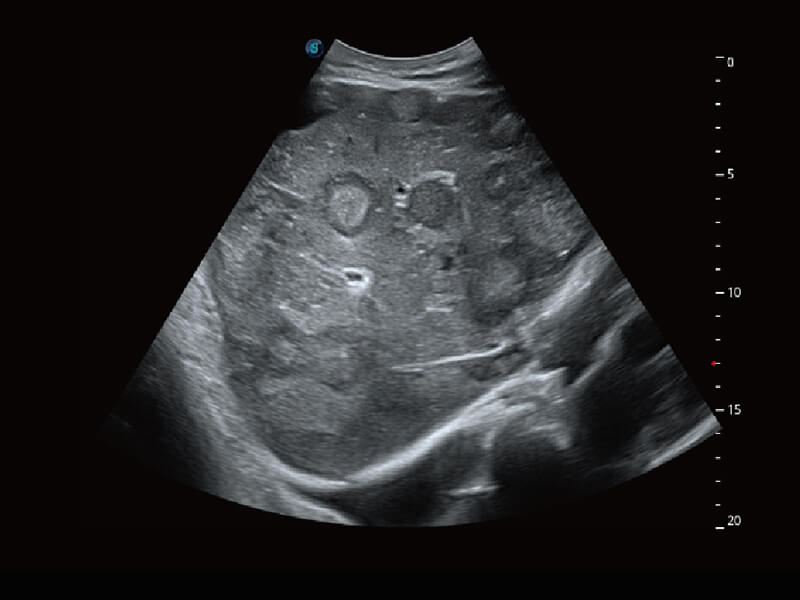

性能优异的硬件架构,极大提升超声系统的运行效率和数据处理能力。相比以往超声成像系统,Wis+平台为您带来极快的响应速度和成像帧频,提升检查流畅度。

超宽频带技术,为容积成像带来优质的二维图像基础,为您呈现丰富的结构细节,栩栩如生地展示宝宝的宫内形态以及各种组织的立体结构。